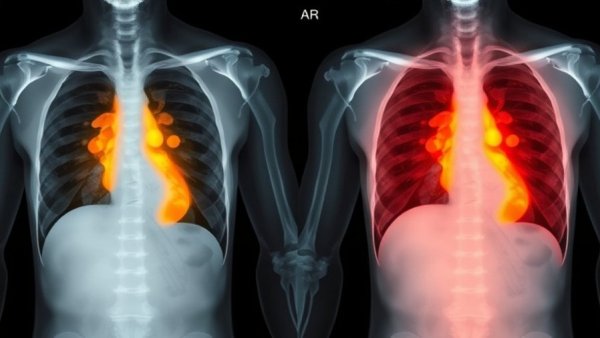

AI algorithms are designed to analyze chest X-rays and generate heat maps that indicate potential zones of infection, thus providing immediate diagnostic insights. This radical shift is a response not only to the famine of radiologists but also to the needs of marginalized communities. For example, a nomadic population in Nigeria is now benefiting from these mobile technologies, allowing them to access care in otherwise unreachable areas.